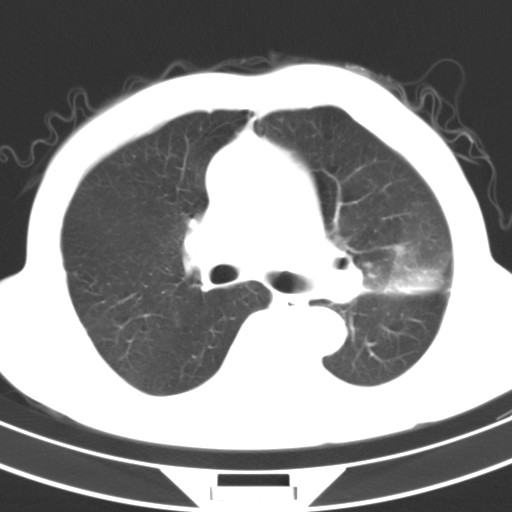

标题: CT18248:男,71岁,糖尿病住院,无发热、咳嗽、咳痰。 [打印本页]

男,71岁,糖尿病住院,无发热、咳嗽、咳痰。

肺气肿,右肺下叶感染。左肺空洞。并与血管连接不排除周围型肺癌。

1.左肺结核伴空洞形成

2.双肺下叶炎症

两肺感染性病变(结核可能性大,有空洞形成)。

左肺结核伴空洞形成